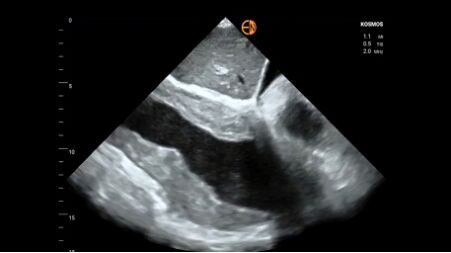

31.下圖為子宮超音波影像,最可能診斷為以下何種疾病? (A)子宮肌瘤(uterine myoma)(B)子宮內膜癌(endometrial cancer)(C)子宮頸癌(cervical carcinoma)(D)子宮腺肌症(adenomyosis)